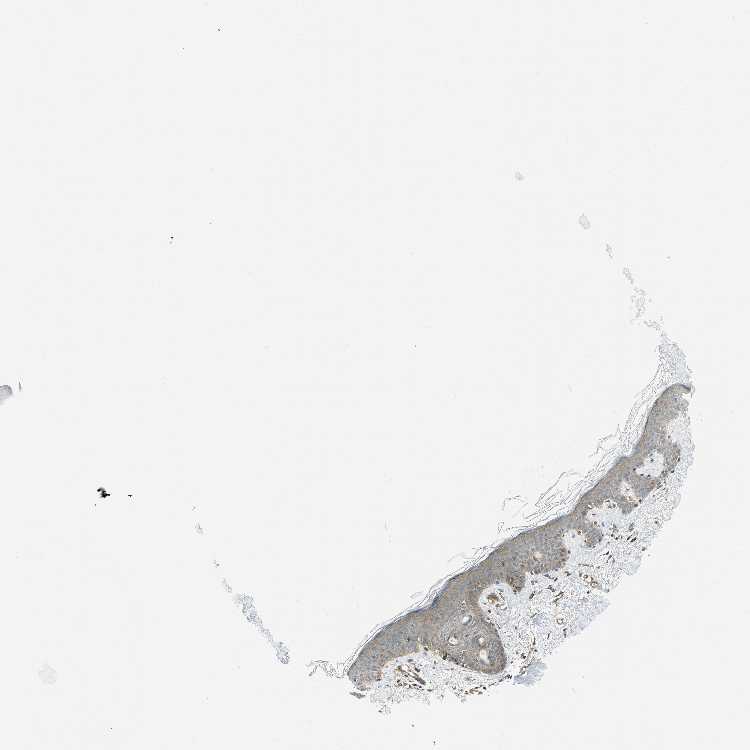

SKIN 1 - Antibody stainingi

Antibody staining in the annotated cell types in the current human tissue is reported as not detected, low, medium, or high, based on conventional immunohistochemistry profiling in selected tissues. This score is based on the combination of the staining intensity and fraction of stained cells.

Each image is clickable and will lead to virtual microscopy that enables deeper exploration of all samples and also displays staining intensity scores, fraction scores and subcellular localization as well as patient and tissue information for each sample.

Antibody CAB017514

Langerhans Low

Fibroblasts Medium

Keratinocytes Low

Melanocytes Low